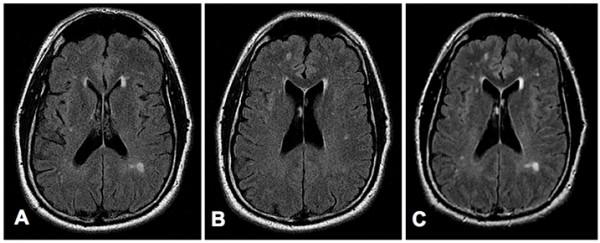

The stromal vascular fraction (SVF) of adipose tissue is known to contain mesenchymal stem cells (MSC), T regulatory cells, endothelial precursor cells, preadipocytes, as well as anti-inflammatory M2 macrophages. Safety of autologous adipose tissue implantation is supported by extensive use of this procedure in cosmetic surgery, as well as by ongoing studies using in vitro expanded adipose derived MSC. Equine and canine studies demonstrating anti-inflammatory and regenerative effects of non-expanded SVF cells have yielded promising results. Although non-expanded SVF cells have been used successfully in accelerating healing of Crohn's fistulas, to our knowledge clinical use of these cells for systemic immune modulation has not been reported. In this communication we discuss the rationale for use of autologous SVF in treatment of multiple sclerosis and describe our experiences with three patients. Based on this rationale and initial experiences, we propose controlled trials of autologous SVF in various inflammatory conditions.

已知脂肪组织的基质血管成分(SVF)包含间充质干细胞(MSC)、调节性T细胞、内皮祖细胞、前脂肪细胞以及抗炎性M2巨噬细胞。自体脂肪组织植入的安全性得到了该手术在整形手术中的广泛应用以及使用体外扩增的脂肪来源MSC的正在进行的研究所支持。马和犬的研究表明未扩增的SVF细胞具有抗炎和再生作用,已产生了有前景的结果。尽管未扩增的SVF细胞已成功用于加速克罗恩瘘管的愈合,但据我们所知,尚未有关于这些细胞用于全身免疫调节的临床应用报道。在本交流中,我们讨论了使用自体SVF治疗多发性硬化症的基本原理,并描述了我们对三名患者的经验。基于这一基本原理和初步经验,我们提议对自体SVF在各种炎症性疾病中的应用进行对照试验。